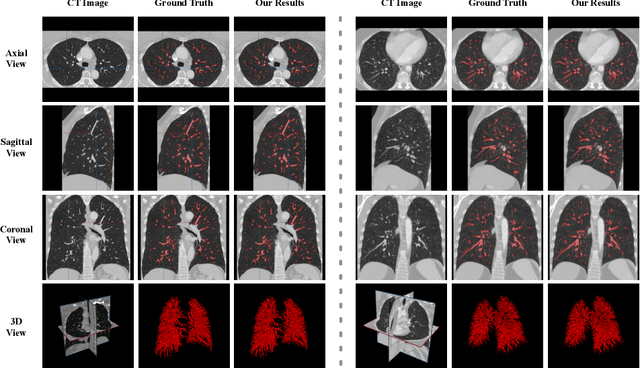

Abstract:Pulmonary vessel segmentation is important for clinical diagnosis of pulmonary diseases, while is also challenging due to the complicated structure. In this work, we present an effective framework and refinement process of pulmonary vessel segmentation from chest computed tomographic (CT) images. The key to our approach is a 2.5D segmentation network applied from three orthogonal axes, which presents a robust and fully automated pulmonary vessel segmentation result with lower network complexity and memory usage compared to 3D networks. The slice radius is introduced to convolve the adjacent information of the center slice and the multi-planar fusion optimizes the presentation of intra- and inter- slice features. Besides, the tree-like structure of the pulmonary vessel is extracted in the post-processing process, which is used for segmentation refining and pruning. In the evaluation experiments, three fusion methods are tested and the most promising one is compared with the state-of-the-art 2D and 3D structures on 300 cases of lung images randomly selected from LIDC dataset. Our method outperforms other network structures by a large margin and achieves by far the highest average DICE score of 0.9272 and precision of 0.9310, as per our knowledge from the pulmonary vessel segmentation models available in the literature.